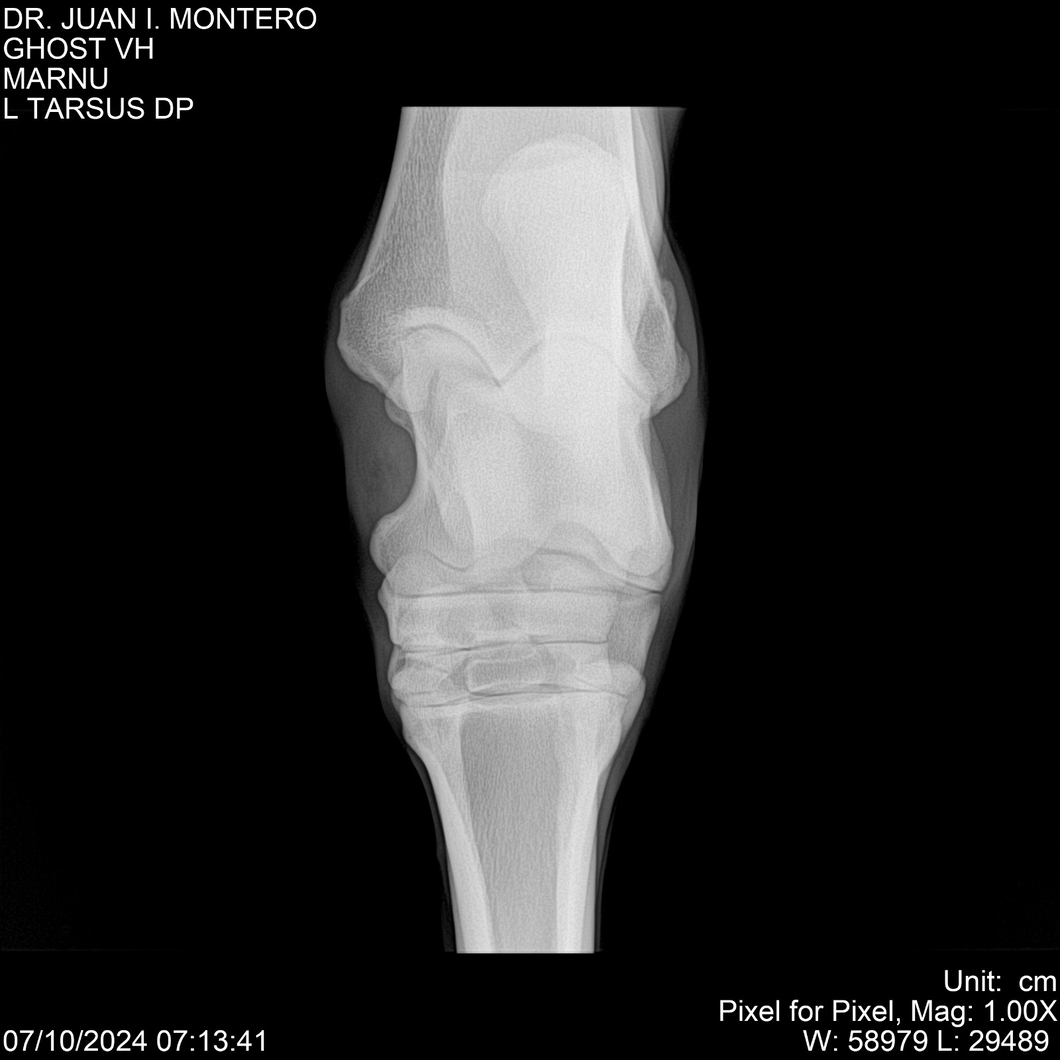

LOTE 15, GHOST VH 🔥 🔥 🔥 Lote Anterior Volver al remate Lote Siguiente Ficha Contacto Montevideo - Ficha del Lote Identificador: #282525 Categoría: Yeguarizos Montevideo - 69 Visualizaciones ClicData Contacto Empresa: Abelenda N. R., Walter Hugo Nombre*: Teléfono* : E-mail* : Mensaje Enviar Registrese gratis Este contenido Exclusivo está disponible sólo para usuarios registrados Ingresar